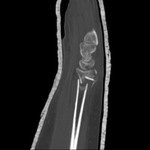

Fixação com placa, após redução aberta, com placa e parafusos colocados em posição volar

Do acervo do Dr. Chaitanya S. Mudgal

As tomografias computadorizadas (TCs) do punho fornecem detalhes excelentes para avaliação da geometria da fratura, do comprometimento articular e do grau de cominuição